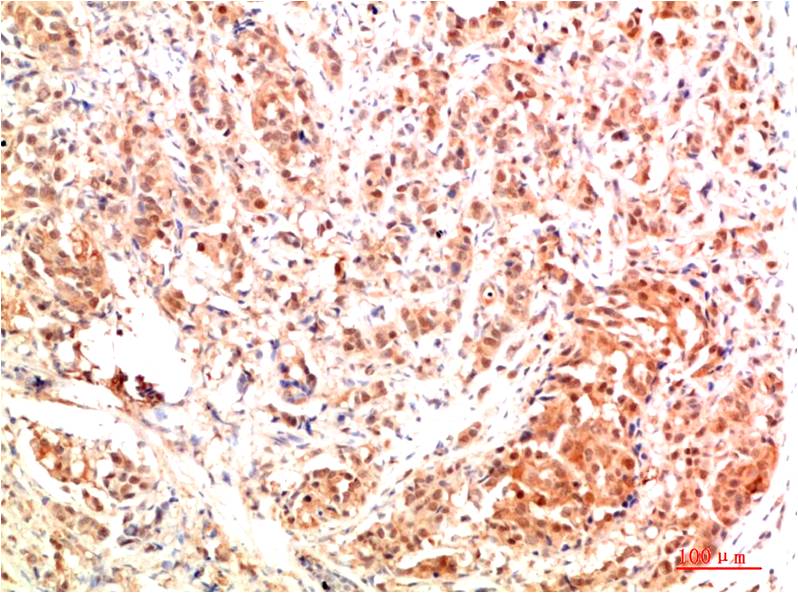

IkB α Rabbit Polyclonal Antibody

Applications :WB, IHC

| Recommended dilutions: | WB 1:500-2,000 IHC 1:50-300 |